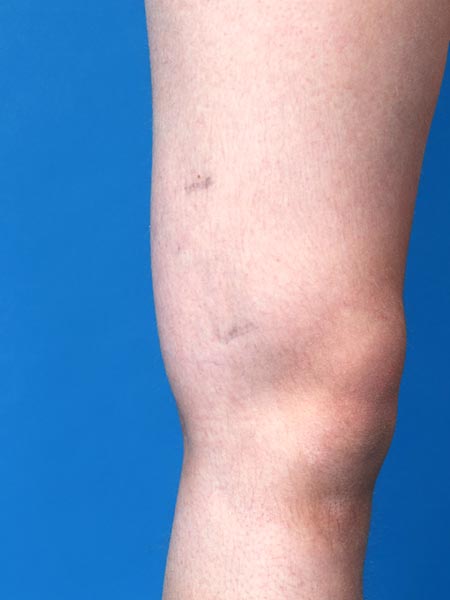

12-jährige Patientin mit umschriebener, relativ weich tastbarer Schwellung am lateralen distalen Oberschenkel. An der Haut an 2 Stellen dysplastische Venen sichtbar. Im Bereich der Schwellung immer wieder Verhärtung und umschriebene Schmerzen durch Thrombophlebitiden in der venösen Malformation (VM).